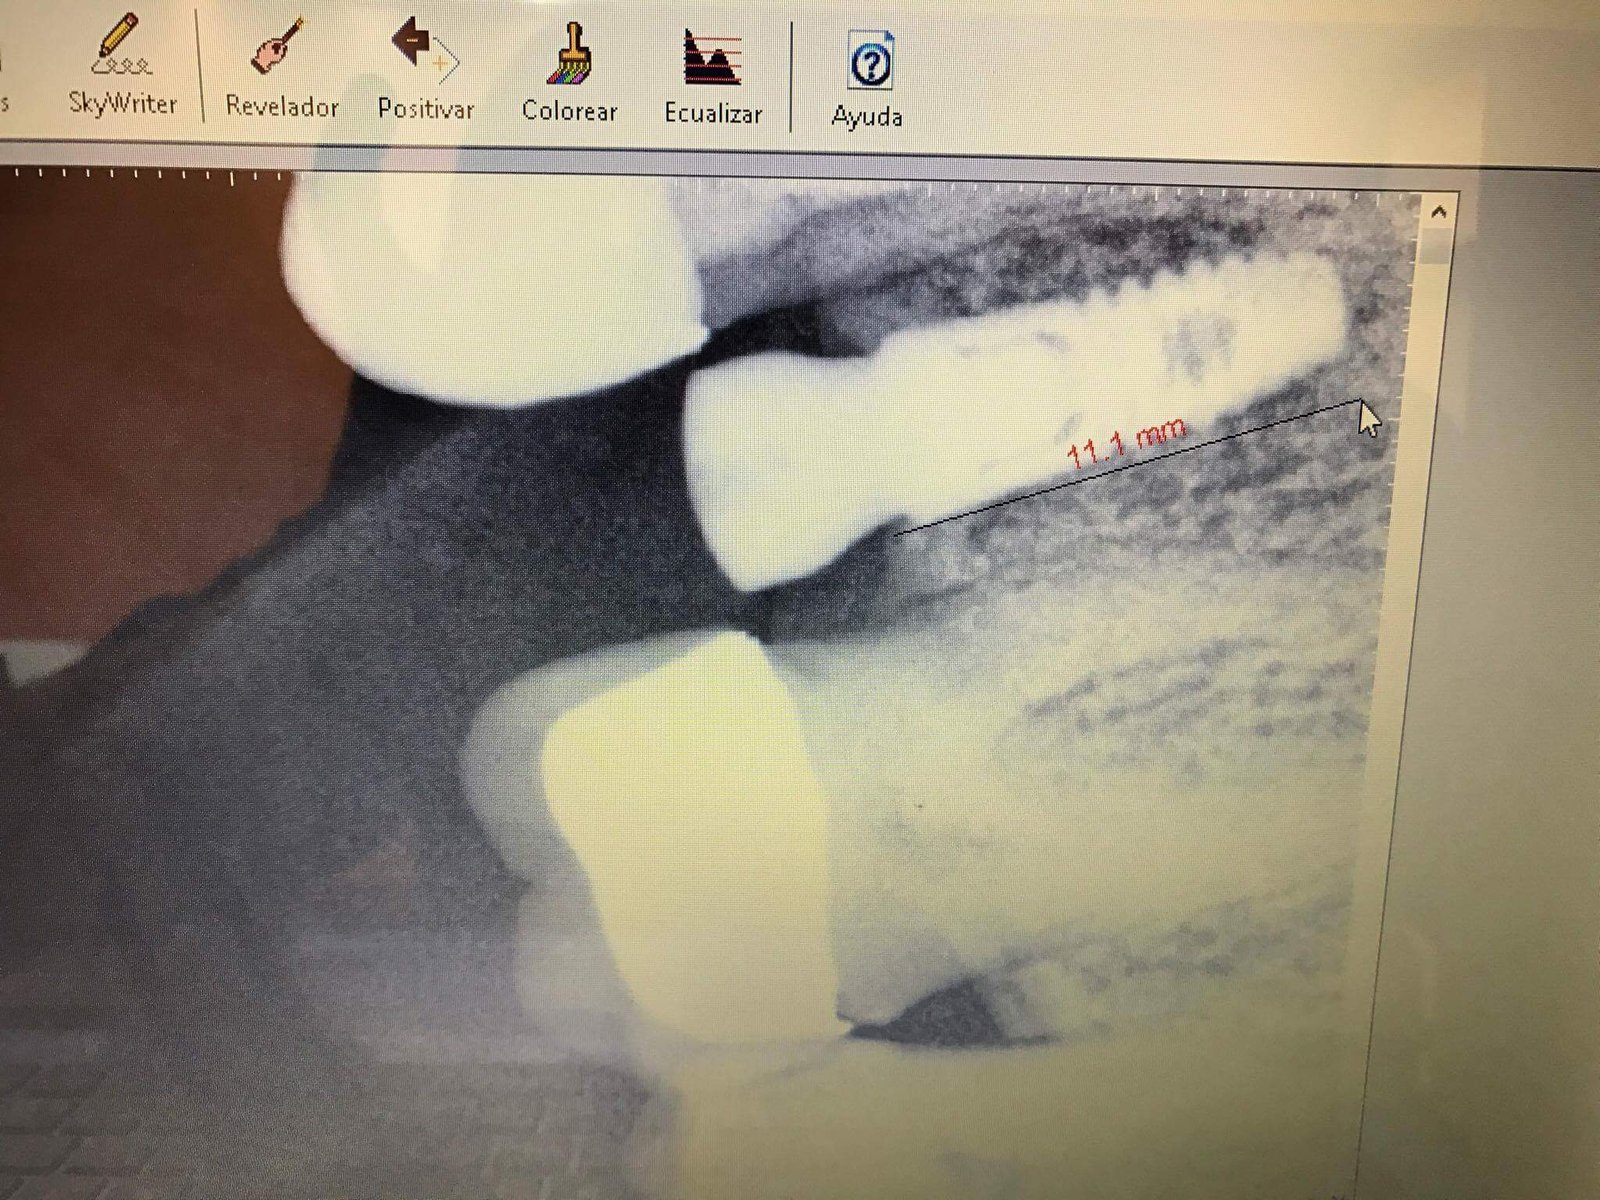

Se presenta paciente con implante dental Astra EV (4.2 por 9mm), con un cicatrizal •5.0 - 3.5. ¿Que aditamento prótesico tendría que adquirir para poder rehabilitar corona cementada, podría desatornillar [...]